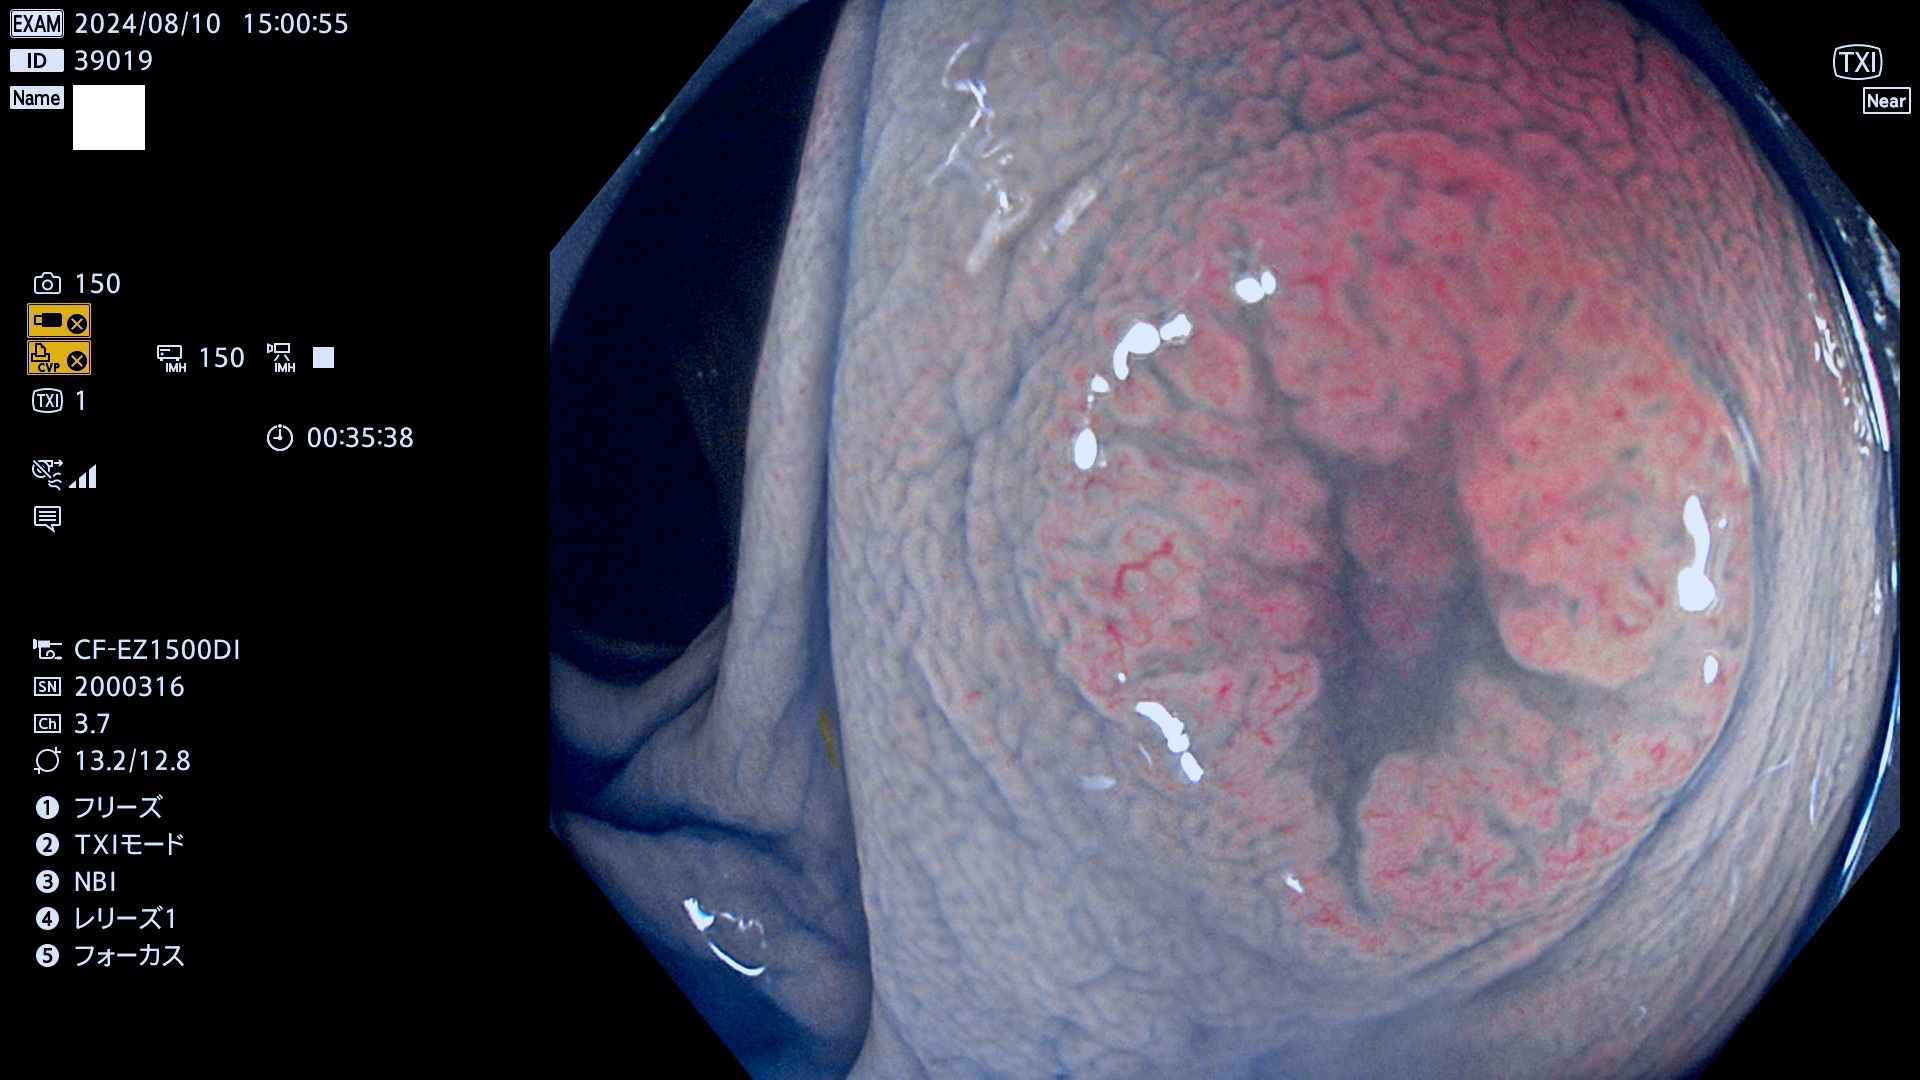

今週のUb、Uc型腺腫

完全に平坦な物をUb、陥凹している物をUcと呼びます。最も発見が難しく危険な病変です。

毎週の検査(木・金・土・日)に発見されたUb、Uc型・腺腫を、その週の日曜の夜にUPし1週間、提示します。

抽出の対象期間 2024年8月8日〜8月11の4日間(30件の検査)11件 (11/30=35%)